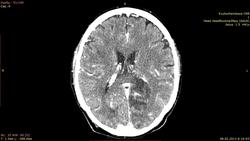

Пациент 67 лет. поступил с признаками онмк. на предыдуших томограммах гомогенное снижение плотности, по типу ишемии. через 10 дней улучшения нет. решили сделать с контрастом.Несколько дней назад у другого пациента с похожими симптомами нашли глиобластому. вот перестраховыаемся. подскажите это формирующаяся киста? как то не совсем нравятся участки контрастирования

Ишемический инсульт.

ишемический инфаркт в б.левой ЗМА. Дайком не качал, но по картинкам - самый обычный.

Опухоль должна иметь собственную ткань. А тут ее нет.

Ишемический инфаркт. Гиральный тип контрастного усиления; исчезает через 8-10 недель после развития заболевания.

Накопление по гиральному типу, ишемия в бассейне ЗМА.